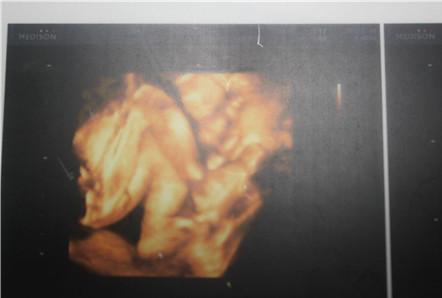

四维彩超看胎儿性别对比图:

胎儿的长和宽的比例

长和宽的比例大于3倍的,男孩子的机率就大些,反之就是女孩子。

看胎儿形状

长条状的是男宝宝可能性大,圆圆的是女宝宝可能性大。